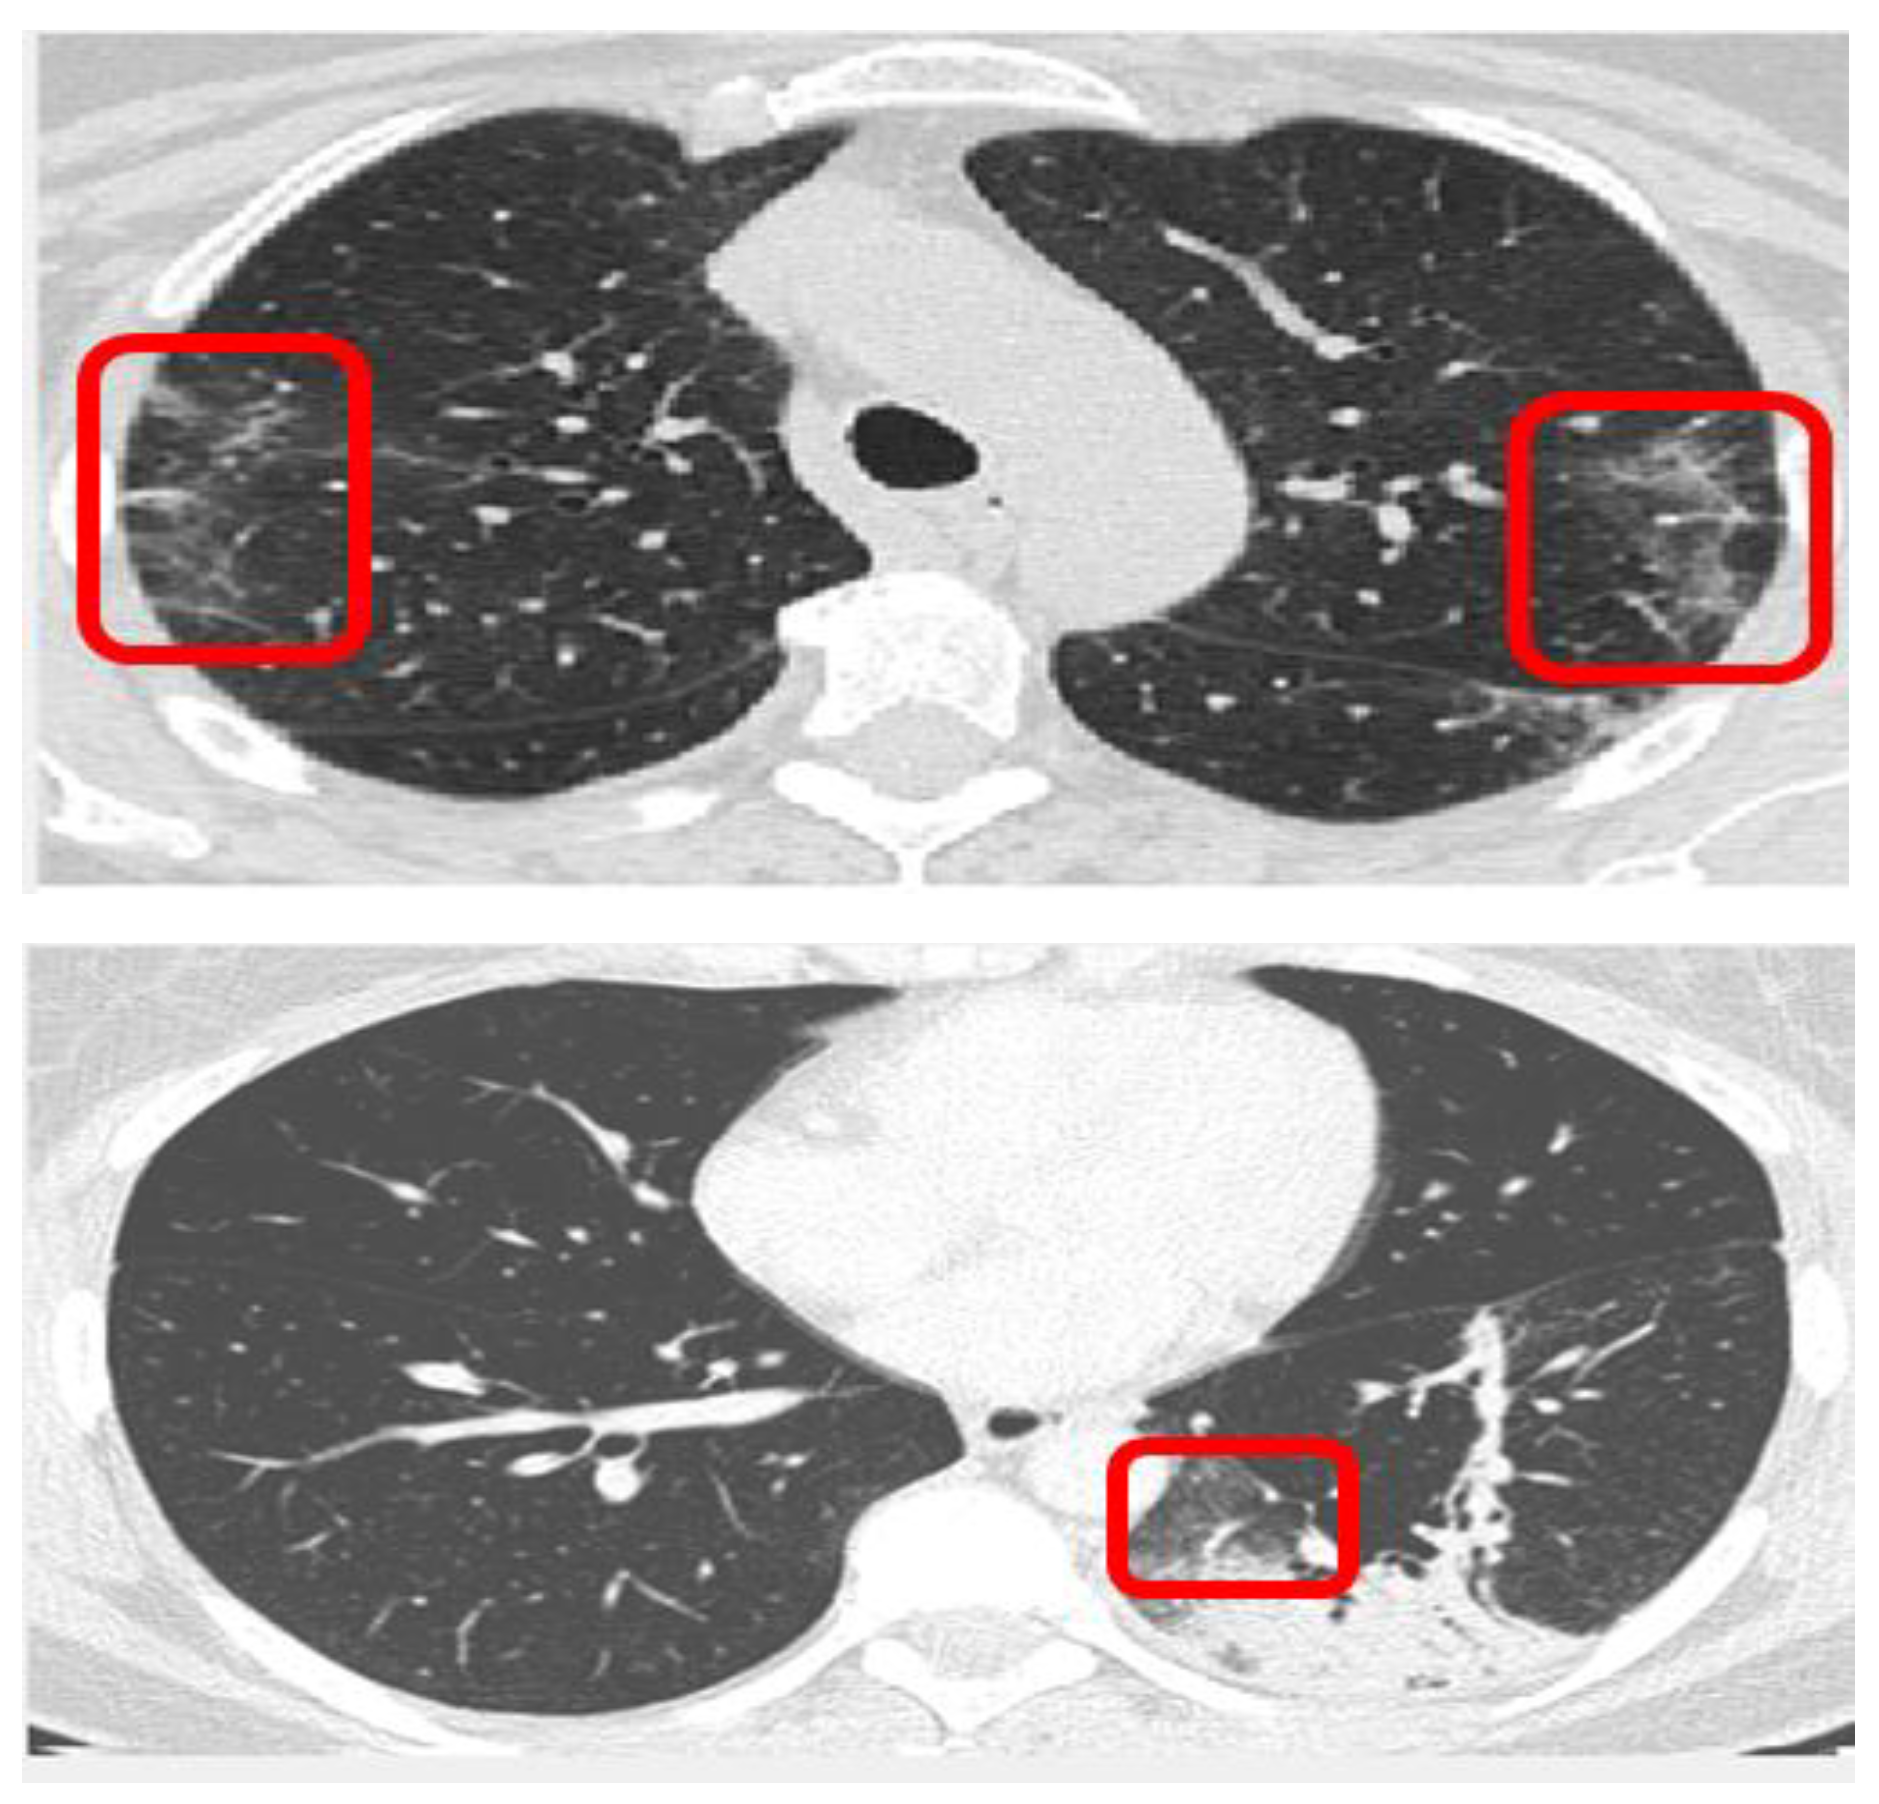

Previous research on CT scan-based diagnostics has related many visual indications to the presence of COVID-19 symptoms. As shown in Figure 1, the red rectangles indicate the existence of ground-glass opacities (GGO), whereas the further distributions of aberrant lesions are the after-effects of the blockages generated [18,19]. GGOs reflect the mucus inflammation present, and the additional distributions of abnormal lesions are the after-effects of the obstructions caused. All cases of GGOs, pleural effusion, and consolidation are classified as COVID-19 indicators in this investigation and are used as factors in the CNN model presented in this case study to classify CT scans.

Figure 1. Examples of COVID-19 signatures in CT scans (red rectangles indicate GGO).